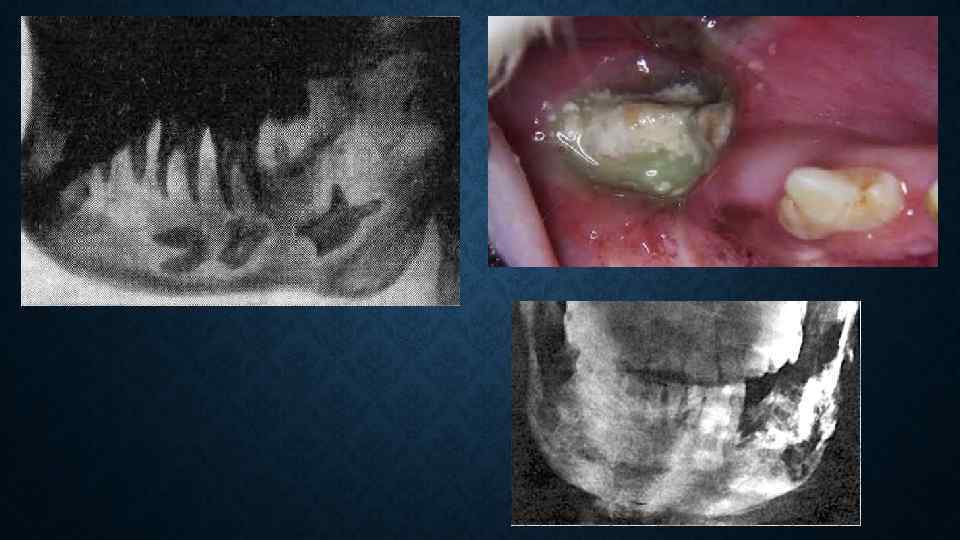

Клинический случай Острый одонтогенный остеомиелит нижней челюсти слева • Клинический диагноз: Острый одонтогенный остеомиелит нижней челюсти слева. Подчелюстной лимфаденит слева. Повышенный рвотный рефлекс

Жалобы • Жалобы: на острую боль в нижней челюсти слева, ноющие боли в подчелюстной области слева, отек на десне и в подчелюстной области слева, ассиметрию лица Жалобы на боли: постоянные, острые, интенсивные боли локализующиеся в нижней челюсти слева, а также ноющие боли в подчелюстной области слева Жалобы общего характера: слабость, недомогание, потеря аппетита, плохой сон, бессонница Жалобы, связанные с нарушением функции органов: Со стороны сердечнососудистой системы тоны сердца приглушены; со стороны дыхательной и пищеварительной систем патологии не обнаружено

История развития заболевания • Считает себя больным около двух дней, когда заболел зуб на нижней челюсти слева, появился отек, повышение температуры тела до 38 С. Обратился за помощью в экстренный кабинет, где был осмотрен дежурным стоматологом-хирургом. Больной был госпитализирован

Предварительный диагноз • • Предварительный диагноз: острый одонтогенный остеомиелит нижней челюсти слева. • Открывание рта не ограничено. В полости рта 37 разрушен на 23, слизистая оболочка вокруг отечная, пальпация болезненная. Перкуссия 37 болезненная. Переходная складка в области 35, 36, 37 сглажена. Слизистая оболочка альвеолярного отростка гиперемирована и отечна как со стороны преддверия полости рта, так и с небной стороны, высыпаний нет. Десны отечны и гиперемированы, не кровоточивы, разрыхлены. Язык нормальной формы и величины, влажный, обложен, выраженность сосочков в пределах нормы. Трещин, прикусов, язвочек нет. Слизистая глотки розового цвета, влажная, гладкая, блестящая, налетов, изъязвлений, рубцов нет. • Обоснование: диагноз поставлен на основании жалоб больного на острые, постоянные, интенсивные боли локализующиеся в нижней челюсти слева; данных анамнеза заболевания о том, что считает себя больным около двух дней, когда заболел зуб на нижней челюсти слева, появился отек, повышение температуры тела до 38 С. ; данных обьективного исследования - незначительная ассиметрия лица за счет воспалительного отека мягких тканей нижней челюсти слева. При пальпации определяется болезненность по наружной поверхности челюсти в области воспалительного очага

План обследования • общий анализ крови, общий анализ мочи, рентгенография нижней челюсти

• данных рентгенографии нижней челюсти: на рентгенографии нижней челюсти слева - очаг деструкции костной ткани в области корней 37 с четким контуром, диаметр 1, 0 см

План и методы лечения 1. Клинико-лабораторное обследование. 2. Вскрытие и дренирование субпериостального абсцесса, удаление 37 зуба под наркозом. 3. Медикаментозная терапия.